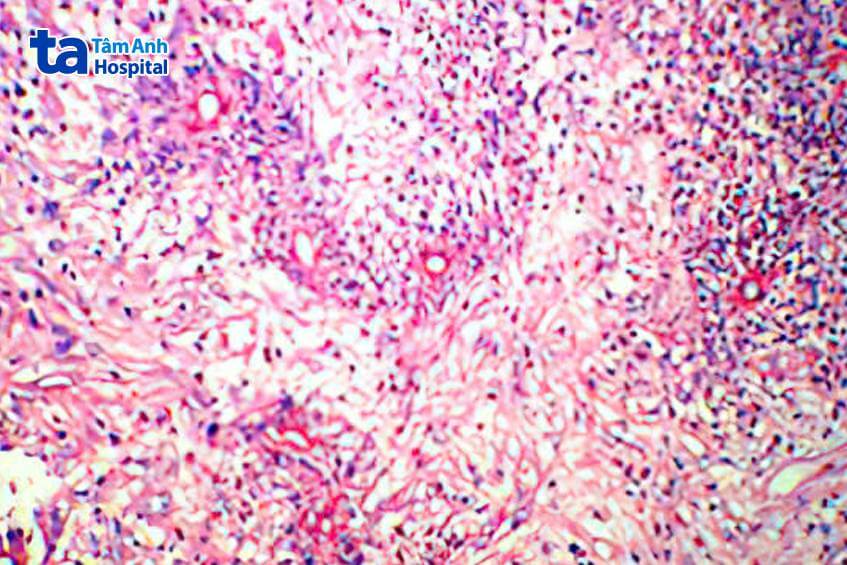

TTƯT.PGS.TS Triệu Triều Dương, Giám đốc chuyên môn Ngoại khoa, cho biết do người bệnh tái phát nhiều lần, bác sĩ hồi cứu lại quá trình mổ và kiểm tra bệnh phẩm được lưu giữ tại bệnh viện trước, hội chẩn cùng bác sĩ Giải phẫu bệnh, chỉ thấy hình ảnh viêm, không có hình ảnh ung thư đặc trưng. Khai thác kỹ tiền sử, gia đình ông Minh có nuôi nhiều thú cưng. Do đã nghỉ hưu, hàng ngày ông dành thời gian chăm sóc, vui chơi cùng vật nuôi. Bác sĩ nghi ngờ có tổn thương viêm do ký sinh trùng.

Kết quả xem xét tiêu bản dương tính với giun đũa chó mèo Toxocara, tổn thương nang dịch phù nề ruột non và mạc treo ruột non. Sau 3 tuần uống thuốc điều trị, ông Minh cải thiện sức khỏe, giảm đau, ăn uống trở lại, hết dịch ổ bụng và không còn tình trạng tắc ruột. Đầu tháng 12, sau gần 1 năm theo dõi thông qua tái khám định kỳ, sức khỏe ông Minh ổn định, không tái phát bệnh.